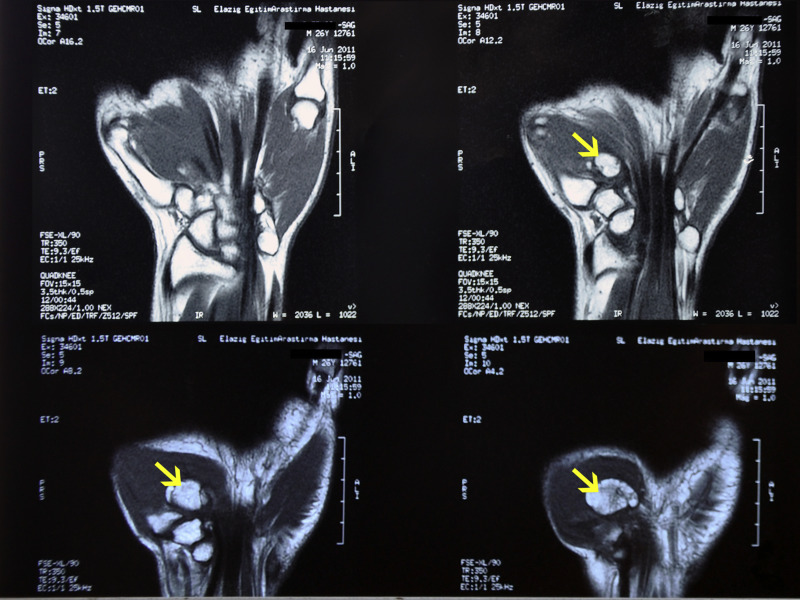

Fig. 1.

Magnetic resonance imaging shows an ossified mass (arrow ) of approximately 25 mm in diameter in the thenar eminence in between the first and the second metacarpal bones.